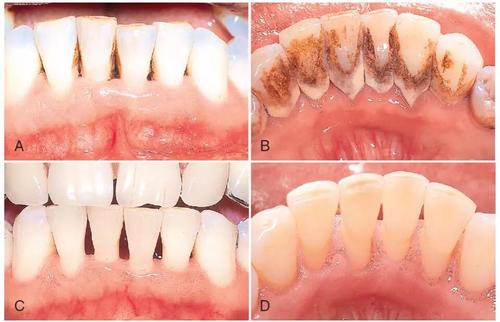

手动器械洗牙就是医务人员用洁牙工具将你牙齿中的软垢结石等一点点刮掉;超声波洗牙主要是通过超声波振动来清除顽固牙石;而喷沙洗牙是利用快速喷出的细盐微粒来清洗牙齿。

对于牙结石特别多的人有的医院会加收费用,因为结石多的人需要花更多的时间,有些一个半小时都洗不干净;而经常洁牙,牙周比较干净的一般四十分钟甚至更少时间可以搞定。

有些诊所是不做龈下洁治的,但是龈下其实更藏污纳垢一点,特别是没有洁过牙的,建议做一下龈下洁治。有些小诊所是因为不会所以不做龈下,只做龈上洁治的话,时间会更快,一般半小时左右就可以做完。